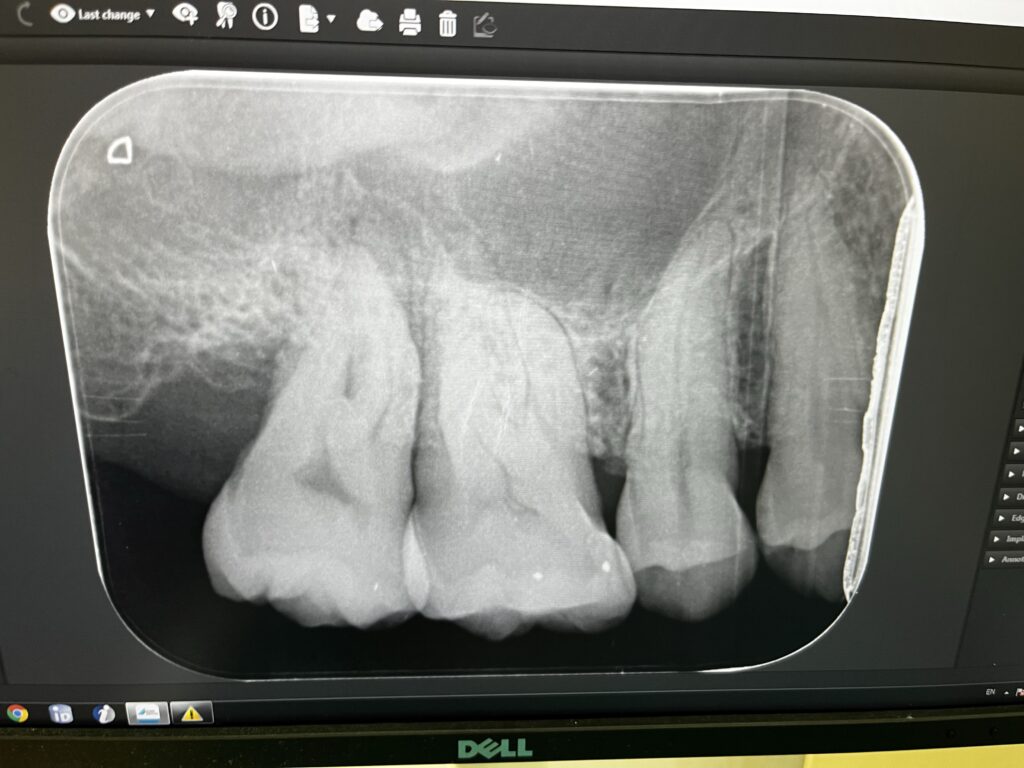

上のレントゲンが奥歯の写真。一番左の歯が痛むところ。そのさらに左が凹んでいて以前の親知らずがあったところ。凹んでいて掃除が難しい。歯周ポケットも1cm以上あってここにゴミが溜まって歯周病になった。

咀嚼で一番大事な奥歯がすでにグラグラしていて、たぶん神経が死んでるらしい。抜きますか?それともまだ歯周病治療しますか?でも歯の神経抜かないと行けないね、みたいな話をされたが、抜くのは保留して再度歯周病専門の先生に再度診てもらうことに。